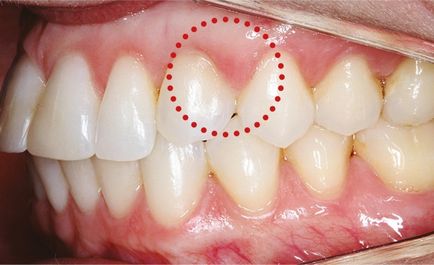

Károsodása fogszuvasodás korai szakaszban gyakorlatilag észrevehetetlen az emberre. Ha a fogfájás kezd bajlódni nyomást a fogat, akkor beszélhetünk a fogszuvasodás kialakulásának folyamatát.

A kezdeti szakaszban a nyaki szuvasodás a fogak közötti

Lehet, hogy a szuvas üreg találkozásánál két foga, így az emberek nem látja magát.

Annak érdekében, hogy azonosítsa a lokalizáció fogszuvasodás, akkor ajánlott az első fájdalom a fogak azonnal keresse fel a fogorvost, amelynek révén megfelelő kezelést.